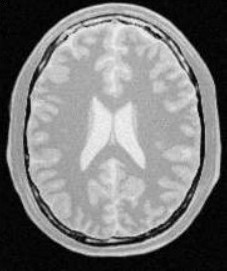

使用人体大脑截面图作为输入图像,选择合适的像素点作为种子像素,生长的结果如下图所示:

| 原始图像 | 连续阈值法 | 邻接连续阈值法 | 置信连接阈值法 |

| 参数 | [150,180] | [150,180] R:3 | Iter:10 factor:2.5 r:5 |

| 结果点数 | 15011 | 7854 | 14643 |